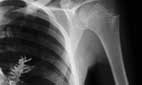

Entonces, los médicos de Artyom Sidorkin, de 28 años, pensaron que extraerían un tumor de su pulmón, pero lo que vieron en la radiografía distaba de ser un grupo de células anormales: era una rama de abeto de unos 5 centímetros de largo.